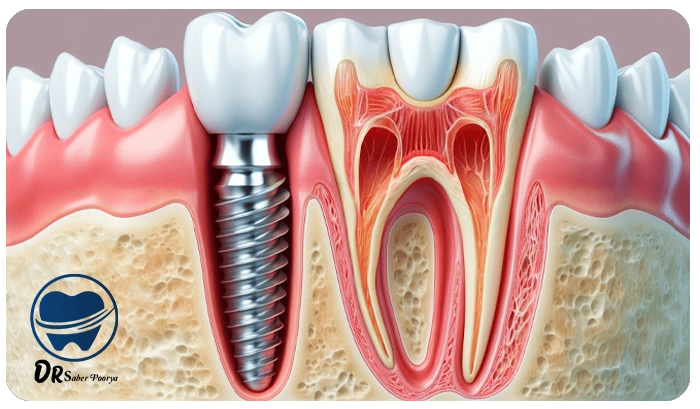

ایمپلنت فوری یا همان “Immediate Implant” روشی است که در آن، بلافاصله پس از کشیدن دندان، پایه ایمپلنت در فک قرار داده میشود و در بسیاری از موارد تاج موقت هم روی آن نصب میگردد.

۱. قرار دادن فیکسچر ایمپلنت

اولین گام در فرایند ایمپلنت، کاشت فیکسچر یا همان پایه اصلی است.

این قطعه کوچک که معمولاً از جنس تیتانیوم ساخته میشود، طی عمل جراحی داخل استخوان فک قرار میگیرد.

فیکسچر نقش ریشه دندان را بازی میکند و پس از جوش خوردن با استخوان، بستری محکم و پایدار برای ادامه مراحل ایمپلنت به وجود میآورد.

۳. نصب اباتمنت ایمپلنت

در مرحله بعد، اباتمنت به فیکسچر متصل میشود. این بخش رابط میان پایه و روکش ایمپلنت است و دندان مصنوعی روی آن سوار خواهد شد.

۴. قرار دادن روکش ایمپلنت

آخرین مرحله، نصب روکش یا تاج دندان است. روکش ظاهری کاملاً شبیه دندان طبیعی دارد و علاوه بر زیبایی، عملکرد جویدن و صحبت کردن را نیز به طور کامل بازمیگرداند.